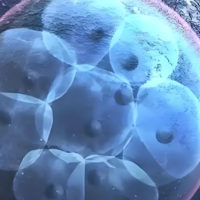

3. 制订化方案:根据失败缘故(如胚胎质量差、内膜容受性低)整合药物或技术(如PGT胚胎检查筛选)。